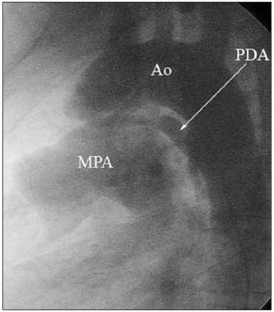

Figure 2.